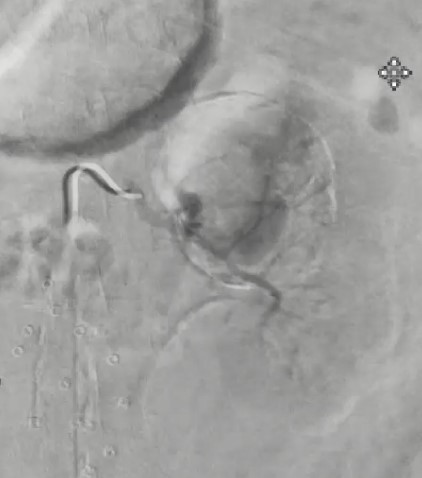

We disengaged the left renal artery with catheter and wire and exchanged our 5F sheath for a 6.5F Destino Twist directional sheath (Oscor), again selected the left renal artery, and advanced the sheath into the proximal renal artery. Next, the Bentson wire was exchanged for a V-18 ControlWire guidewire (Boston Scientific), and a 6-mm x 25-mm Viabahn covered stent (Gore Medical) was deployed across the neck of the aneurysm, thereby excluding the aneurysm from arterial circulation and maintaining perfusion to the left kidney (Figure 3). Completion angiogram demonstrated adequate deployment of the covered stent, and the right femoral access site was closed with a Perclose ProGlide Suture-Mediated Closure device (Abbott) in standard fashion.